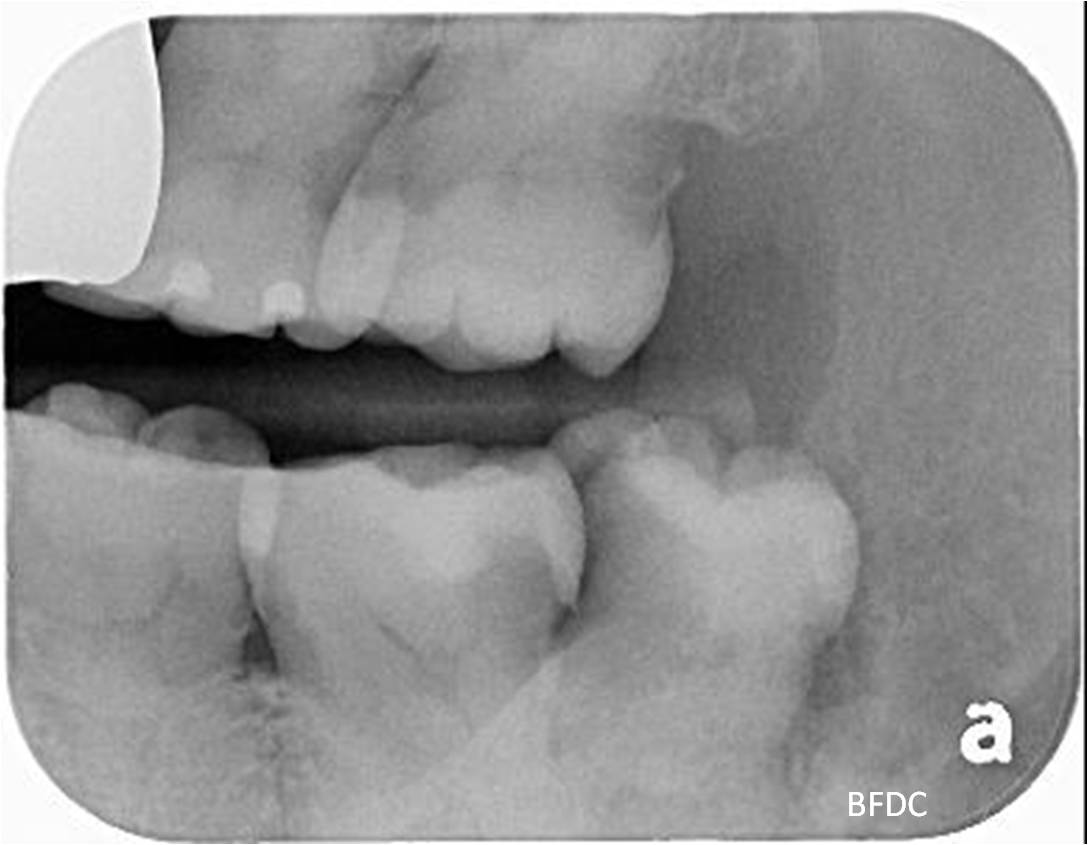

治療前,阻生齒塞食物,清潔不易,深度蛀牙

治療前,深度蛀牙